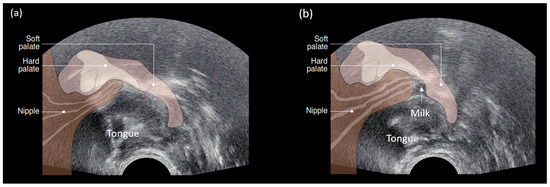

10. Sucking Swallowing and Breathing

Suck Swallow Breath Co-Ordination

Milk removal by breastfeeding infants